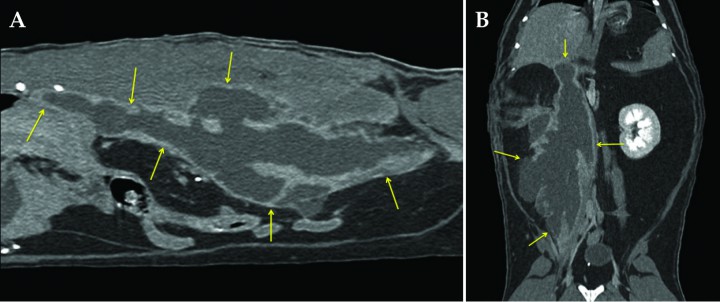

Ante la dificultad de establecer unos límites claros de la lesión se decide hacer una TC prequirúrgica (Fig. 4). La opacidad radiográfica tejido blando presentaba un contenido densidad líquido con una cápsula bien definida en la periferia de la mayor parte de la lesión, realzando de manera marcada desde la fase arterial de contraste. Los límites del absceso se extendían lateral y dorsalmente afectando a la musculatura, fascias y tejido adiposo paraespinal, con leve reactividad de la grasa perilesional. La cavidad pleural y el parénquima pulmonar no estaban afectados. No se identificó ningún cuerpo extraño que pudiera justificar el cuadro.

<p>Imágenes de Tomografía Computarizada en (A) corte sagital y (B) dorsal de la cavidad abdominal post-contraste ventana de tejido blando mostrando el absceso en su extensión máxima (flechas amarillas). Se observa la cápsula con marcado realce en la mayor parte de la extensión de la lesión, que no sólo se circunscribe a la porción ventral de la musculatura espinal, sino que también se proyecta dorsal entre los procesos transversos de las vértebras lumbares 3 a 5 aproximadamente.</p>

Imágenes de Tomografía Computarizada en (A) corte sagital y (B) dorsal de la cavidad abdominal post-contraste ventana de tejido blando mostrando el absceso en su extensión máxima (flechas amarillas). Se observa la cápsula con marcado realce en la mayor parte de la extensión de la lesión, que no sólo se circunscribe a la porción ventral de la musculatura espinal, sino que también se proyecta dorsal entre los procesos transversos de las vértebras lumbares 3 a 5 aproximadamente.